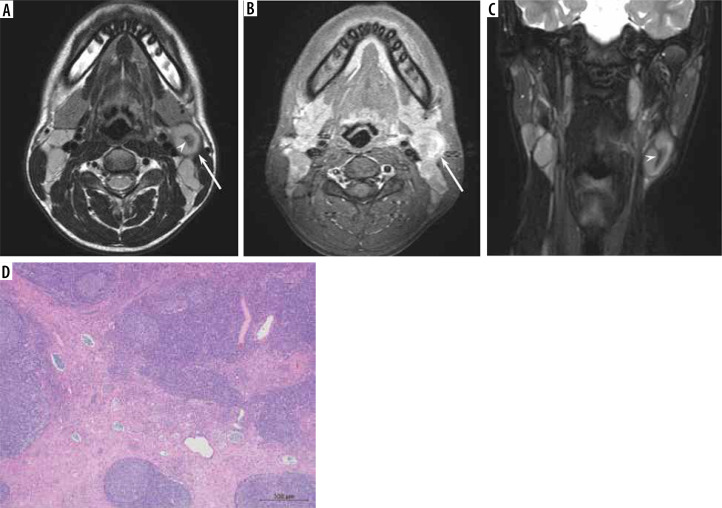

Results: The maximum diameter (22.4 ± 6.9 vs. 33.3 ± 16.0 mm, p < 0.01), minimum diameter (15.8 ± 3.6 vs. 22.3 ± 8.5 mm, p < 0.01), and SUVmax (6.9 ± 2.7 vs. 12.8 ± 8.0, p < 0.01) of the lesion were lower in reactive lymphadenitis than in nodal lymphoma, respectively. T2-hypointense-thickened capsules > 2 mm (46% vs. 14%, p < 0.05) and T2-hypointense areas converging to the periphery (15% vs. 0%, p < 0.05) were more frequently observed in reactive lymphadenitis than in nodal lymphoma, respectively. Hilum of nodes on T2-weighted images (54% vs. 22%, p < 0.05) and diffusion-weighted images (69% vs. 30%, p < 0.05) were more frequently demonstrated in reactive lymphadenitis than in nodal lymphoma, respectively.

Conclusions: Reactive lymphadenitis had a smaller size and lower SUVmax. The presence of T2-hypointense-thickened capsules, T2-hypointense areas converging to the periphery, and hilum of nodes were signs of reactive lymphadenitis.